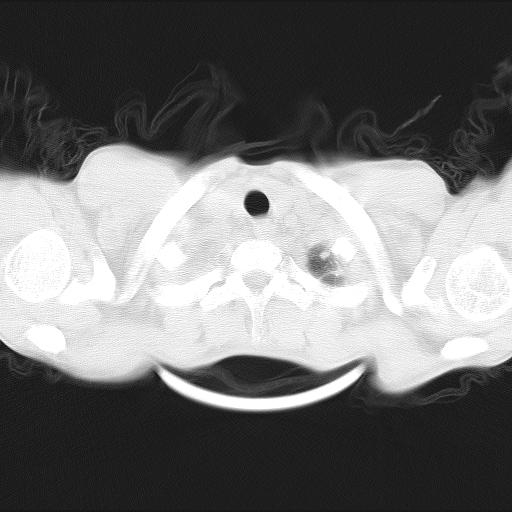

男性,44岁,结核病史多年。现胸闷气短,咳嗽,偶咳血。

1)两肺继发性肺结核伴空洞形成,左肺多发性结核球。2)右侧大量胸腔积液伴右肺部分膨胀不全。3)纵隔淋巴结肿大。

1,双肺多发结节 并空洞影改变, 左侧胸腔积液并部分包裹, 结合原病史首先考虑结核. 但也不除外其它.

2,左侧有一根肋骨陈旧性骨折? 建议追查 .

吉大一院胸水抽检结果:结核性胸水